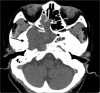

Figure 1:

(a) Plain CT brain. Destructive clival mass involving the foramen magnum (black arrow). (b) Plain CT brain. The presence of intratumoral calcification. Extension of the mass into the foramen magnum with compression onto the medulla (black arrow).

Figure 2:

(a-c) Contrast MRI brain. A lobulated T1-weighted hypointense and T2-weighted hyperintense clival mass with moderate heterogeneous contrast enhancement, showing a honeycombing appearance (white arrows). (d) Contrast MRI brain. Extension of the mass into the foramen magnum with compression onto the brainstem. (e) Contrast MRI brain. Inferior extension with dens erosion (white arrows).

Figure 3:

(a and b) Contrast MRI brain. Lateral extension of the mass into the right middle cranial fossa (white arrow), right cavernous sinus, and right petrous apex with compression onto the right mesial temporal lobe (black arrow). Posterior extension onto the midbrain was also evident (dotted black arrow). (c) Contrast MRI brain. Superior extension of the mass with compression on pituitary stalk and optic chiasm.